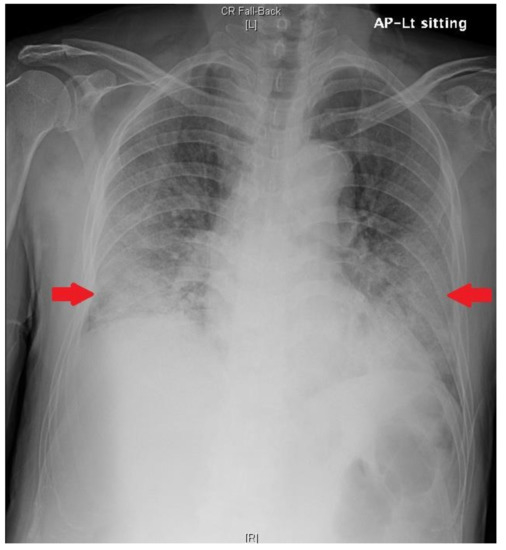

| Chest radiography | GGO in BLLF | Increased GGO | Increased GGO | Decreased GGO | Decreased GGO | Decreased GGO | No interval change | No interval change |